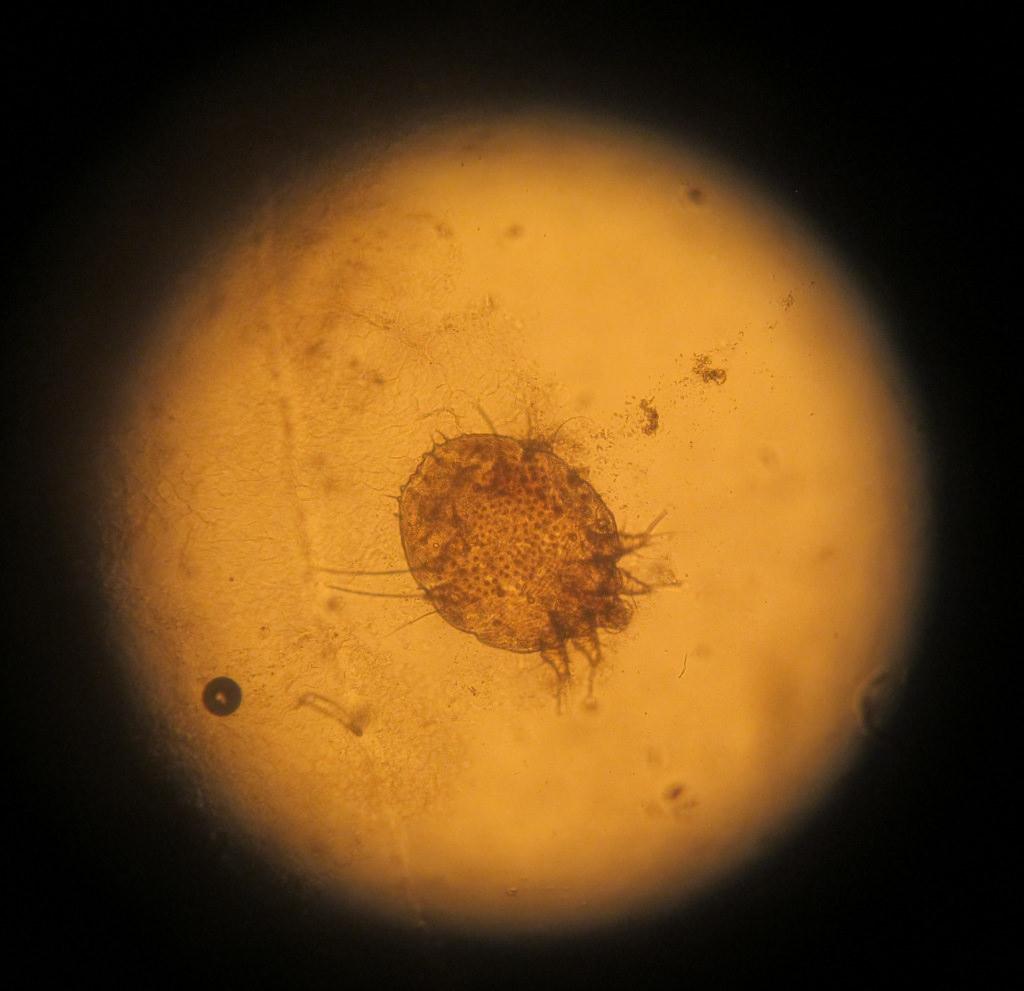

Микроскопия – основной метод определения диагноза, так как возбудитель болезни настолько мал, что не виден невооружённому глазу. С кожи берут множество глубоких и поверхностных соскобов.

Клеща можно обнаружить с помощью молочной кислоты. Одну каплю (40%) нужно нанести на любое поражение и подождать 5 минут. После разрыхленную кожу можно соскоблить острой ложкой, пока не появится капиллярное кровотечение. Полученный эпидермис нужно нанести на предметное стекло и посмотреть на него под микроскопом. Метод позволит определить большинство паразитов и продуктов их активности.

Примечание! Оба вида настолько малы, что рассмотреть их можно только под микроскопом – не более 0,5 мм. Микроскопические клещи питаются отмершими клетками кожи, выделениями сальных желез, клетками из волосяных фолликулов.

После визуального обследования и беседы с пациентом для уточнения диагноза дерматолог назначает микроскопическое исследование. Материал для анализа берут путём соскоба эпидермиса с поражённых участков кожи. Также рекомендуется подвергнуть анализу ресницы, взятые в разных частях глаз. Экспресс-анализ даёт возможность получить мгновенный результат. В ходе исследования обнаруживаются взрослые особи клеща, их яйца и сброшенные хитиновые оболочки. Чтобы перед дерматологом предстала полная картина плотности заселения кожи клещом, рекомендуется не умываться в течение суток перед обследованием. Значение для постановки диагноза в данном случае имеет не сам по себе факт обнаружения клеща, а численность и активность паразита, о которой свидетельствует количество личинок и яиц.